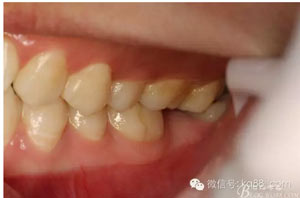

圖2.術(shù)前口內(nèi)照:37未萌出。38牙冠近中傾斜?;颊哒衬ど珴烧?,無瘺管、無滲出。